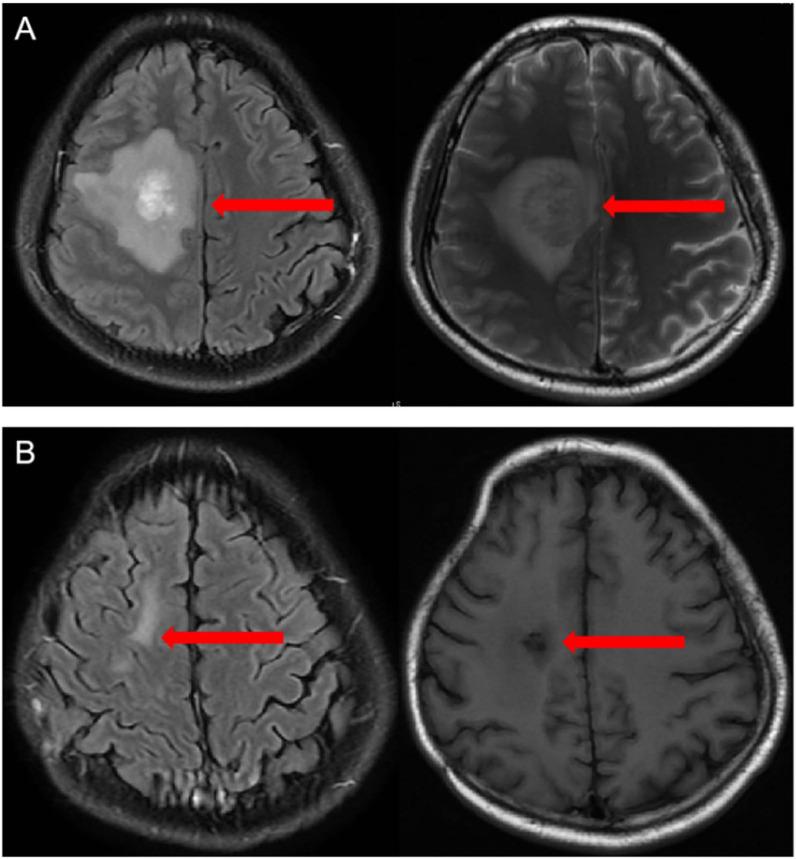

Here, we report a 33-year-male with secondary central diffuse large B-cell lymphoma(CNSL) who develpoed double CRS following sequential infusion of Anti-CD22 and Anti-CD19 CAR T cells after autologous hematopoietic stem cell transplantation(ASCT). On d+5, the patient developed high fever, along with chilly sensation, shivering, headache, blood oxygen desaturation, shock, weakness, severe thirst, and heart rate decline. IL-6 and ferritin increased significantly. The patient was diagnosed with the first CRS (grade 3). On d+36, the patient again had a persistent fever(T>39C) and limbs rash. IL-6 and ferritin again increased significantly on d+38. After exclusion of infection, a diagnosis of double CRS was made. The patient's symptoms were completely relieved after receiving tocilizumab, glucocorticoids, and other supportive treatments on d+45.On d+90, contrast-enhanced MR angiogram shows that the lesion basically disappeared, indicating the patient had achieved CR. At the end of the follow-up at d+150, the patient was functioning normally without any sequelae.

在这里,我们报告了一例 33 岁男性,在自体造血干细胞移植(ASCT)后序贯输注抗 CD22 和抗 CD19 CAR T 细胞后发展为继发性中枢弥漫性大 B 细胞淋巴瘤(CNSL)的双重 CRS。在 d+5,患者出现高热,伴有发冷、寒战、头痛、血氧饱和度下降、休克、乏力、极度口渴和心率下降。IL-6 和铁蛋白显著增加。患者被诊断为首次 CRS(3 级)。在 d+36,患者再次出现持续发热(T>39°C)和四肢皮疹。在 d+38,IL-6 和铁蛋白再次显著增加。在排除感染后,诊断为双重 CRS。在 d+45,患者接受托珠单抗、糖皮质激素等支持治疗后症状完全缓解。在 d+90,增强磁共振血管造影显示病变基本消失,提示患者达到完全缓解。在 d+150 的随访结束时,患者功能正常,无任何后遗症。